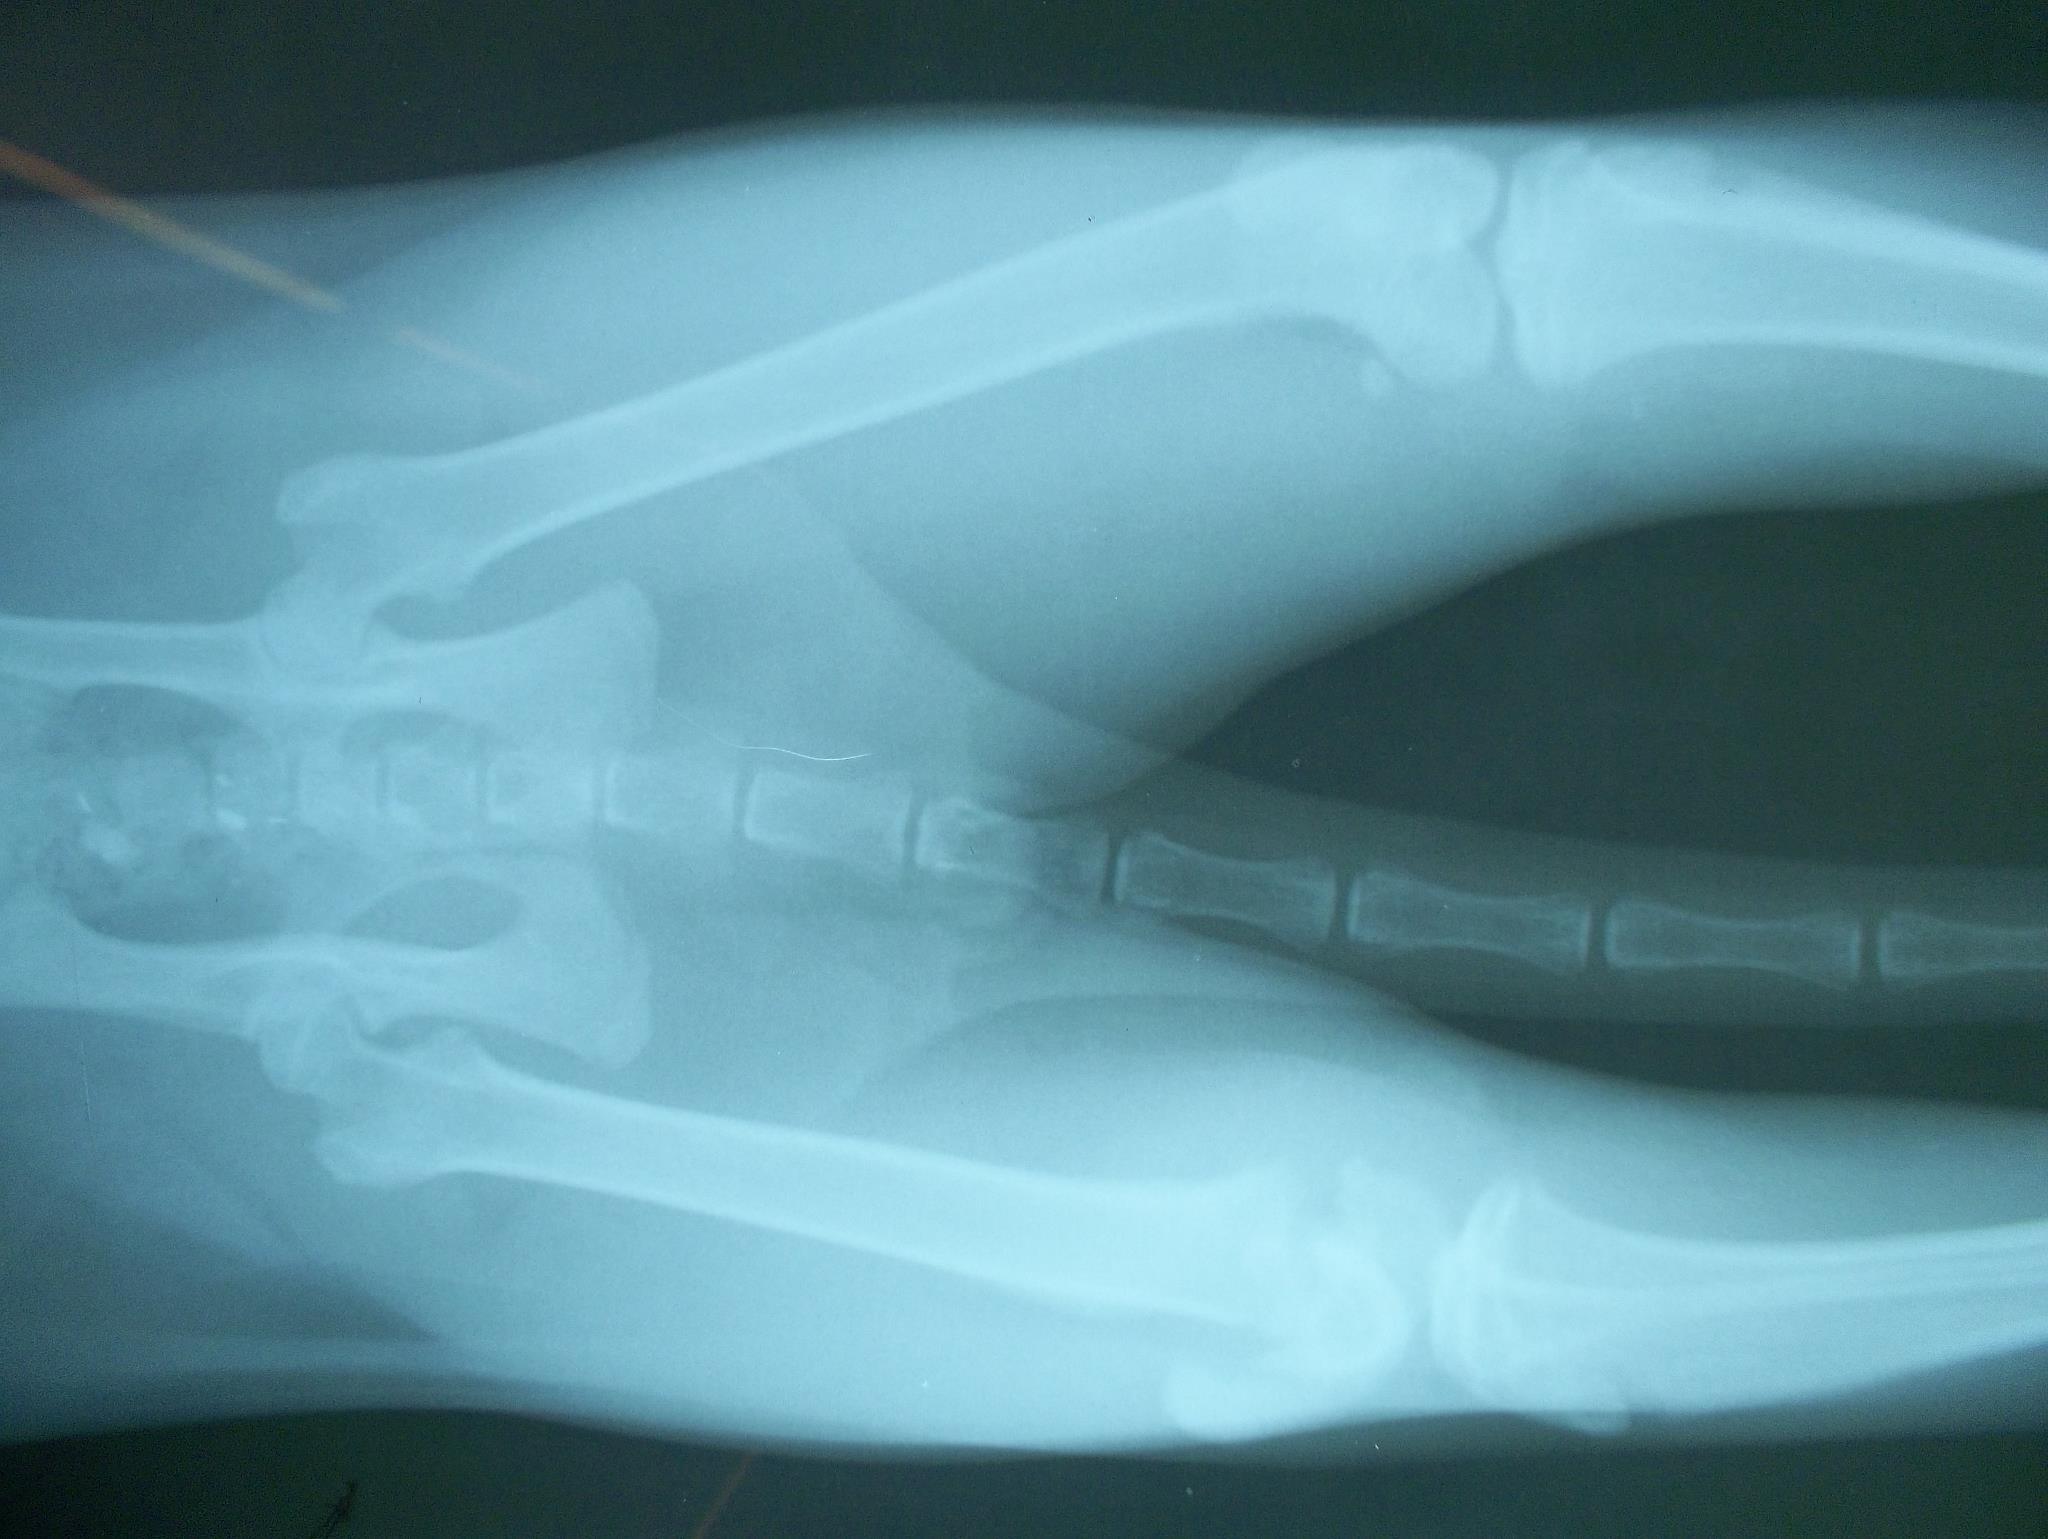

- 編號: 1356

主題: 媽祖廟的骨折公貓 申請者姓名: 許桂菱 花色: 申請日期: 2012-11-11 23:52:53 申請者部落格: 申請者臉書網址: 所在縣市/合作醫院: 台中市/崇德動物醫院 治療費用: 12000元 需求人數: 13人 已結案 (2013-06-27 14:00:26) 報名人員: 馬豆漿(已付款)、kelly(已付款)、Ellen Chou、吉兒(已付款)、Abby Chen、Rachel Ko(已付款)、Hoo Ga(已付款)、Sky(已付款)、Sky(已付款)、Sky(已付款)、Sky(已付款)、Sky(已付款)、Sky(已付款)、馬豆漿 x2(已付款)、 候補人員: 動物病情說明: 在鹿港新祖宮媽祖廟的公浪貓,已經完成TNR了,但沒有溫暖的家的保護下,卻因不明外力造成右後腳骨折,10/10進行骨折手術及一個月的住院療養,於11/9放回原地,會持續做追蹤觀察,各位愛護流浪動物的朋友們能幫忙讓牠重新有健康的貓生~